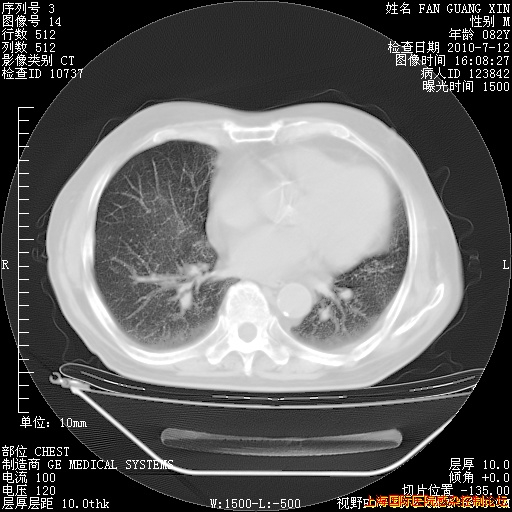

今天复查CT

今天CT

整整相隔30天的肺部CT好像有所好转啊。甲强龙减量第3天,需要观察体温。

海管,自昨日你和我通完话后,不知您岳父消化道症状有无缓解?体温怎样?阅读7.12日胸部ct,个人认为目前激素治疗是有效的,甲强龙减量是适宜的。因在抗痨治疗,需密切观察肝功、肾功能和血常规。不过,老年、长期住院和大量使用激素,很担心菌群失调发生